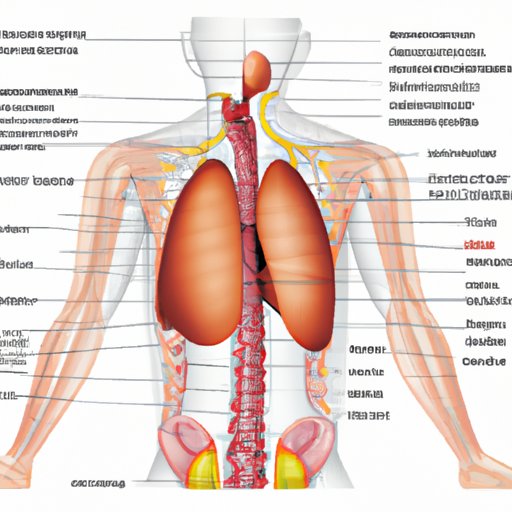

Understanding the Circulatory System: Which Blood Vessels Carry Impure Blood

This article explains the role of blood vessels in the circulation of impure blood in the circulatory system. It also discusses the heart’s role in blood circulation, specific diseases that impact blood circulation, and how impure blood is filtered and transported back into circulation.

The Pulmonary Trunk: Understanding the Heart’s Connection to the Lungs

The pulmonary trunk plays a vital role in regulating the amount of oxygenated blood in the body. This article will explore everything you need to know about the heart’s connection to the lungs, with a focus on the anatomy of the heart, the function of the pulmonary trunk and its connection to the right ventricle, and common issues associated with the pulmonary trunk.

The Atrium: Anatomy, Function, and Significance in Medicine, Architecture, and History

Explore the anatomy, function, and historical significance of atria in medicine, architecture, and history. Learn about the crucial role of atria in the circulatory system and their use as a key design feature in building construction.